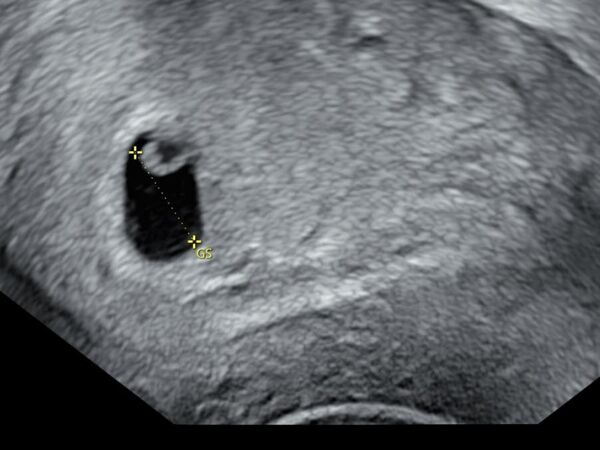

鄭家純透露,原本已經懷孕九週,但在昨(6)日的產檢中確認胚胎停止發育,必須終止妊娠。她表示,半個月前產檢時,醫師就曾提醒胎囊發育較晚,當時還抱著一絲排卵期延後的希望,沒想到最終還是沒能照到心跳。

▲鄭家純懷孕9週後流產。(圖/翻攝自Facebook/鄭家純)

早期流產的機率約15~20%,主因是胚胎染色體異常而發育停止。以我自己的新鮮血淚經驗為例,半個月前產檢發現胚囊發育晚了一週。

醫生說有兩個可能,一個是排卵期晚一週,另一個可能就是胚胎有狀況,下次產檢若沒有照到心跳就是確定停止發育,需安排終止妊娠。

昨天傍晚我開始少量出血,過2小時後出血量變多開始腹痛,就立刻去急診,在醫院時陸續有排出血塊,照了陰道超音波確認胎囊大小與半個月前產檢時一樣,目前的處置就是回家休息吃止痛藥,等體力恢復後回台灣做後續。